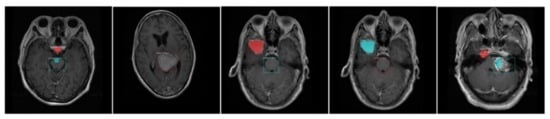

- We have created the annotations which are essential for the training of the proposed model because available datasets do not have a bounding box and mask ground truths (GTs).

3.2. Annotations